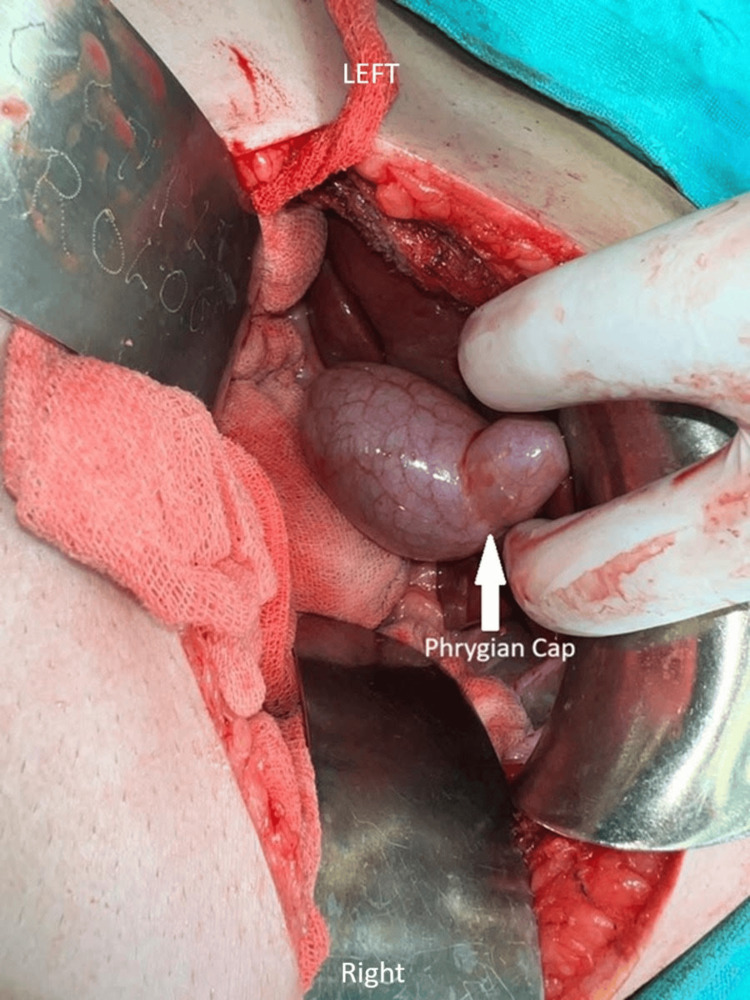

Once the reconstruction was complete, the incisions were meticulously closed in layers to promote proper healing, and a drain was inserted to prevent fluid accumulation in the abdominal cavity, ensuring optimal postoperative recovery. Postoperative surveillance for dehiscence or fistula involved monitoring the surgical site and the patient’s overall condition to detect any signs of complications, including visual inspection of the incision site for redness, swelling, or discharge, and gentle palpation for tenderness and abnormal tissue characteristics. Additionally, the patient was asked about any symptoms experienced, such as increased pain or fever. Throughout the procedure, utmost care and precision were exercised to minimise complications and maximise the patient’s chances of a successful outcome. Additionally, the incidental finding of the Phrygian cap of the gallbladder was noted and managed appropriately within the context of the overall surgical plan. This anatomical variant was meticulously removed along with the primary focus of the surgery. The Phrygian cap of the gallbladder is shown in Figure 1. Computed tomography showing the abnormal gallbladder and Phrygian cap is represented in Figure 2.

The incidental discovery of a Phrygian cap of the gallbladder during a Whipple’s procedure for pancreatic head cancer in a 48-year-old female presents a unique and noteworthy finding. The Phrygian cap anomaly, characterised by a fold or hooding of the gallbladder fundus over the body, is a rare congenital variation often detected incidentally during imaging or surgical procedures [ref. 8]. In this case, the discovery of the Phrygian cap adds a layer of complexity to an already intricate surgical intervention for pancreatic head cancer. The presence of a Phrygian cap may alter the usual anatomical landmarks, requiring adaptability and precision to avoid accidental injury to the gallbladder or bile ducts [ref. 5].

In the case of a 65-year-old female reported by Kulkarni et al., the Phrygian cap of the gallbladder was discovered during an emergency exploratory laparotomy undertaken for a sealed-off perforation at the pyloric part of the stomach [ref. 9]. In our case of a 48-year-old female, it was incidentally noted during a Whipple’s procedure performed for pancreatic head cancer. Both cases involve the identification of a gallbladder anomaly during surgical intervention for other conditions. However, the approach to managing the gallbladder anomaly differs significantly between the two cases [ref. 9]. In our case, where the patient underwent a Whipple’s procedure, the Phrygian cap was meticulously removed along with the primary focus of the surgery, namely pancreatic head cancer. This approach aligns with the principle of comprehensive surgical intervention aimed at addressing all identifiable pathologies within the operative field.

The case report details the management of obstructive jaundice and pancreatic head cancer in a 48-year-old female, complicated by the incidental discovery of a Phrygian cap of the gallbladder during Whipple’s procedure. The treatment involved CBD stenting for jaundice and Whipple’s surgery for cancer, with meticulous attention to the incidental findings. Surgical adaptability and careful decision-making were crucial, highlighting the importance of addressing primary and incidental pathologies for optimal patient outcomes. Postoperative monitoring and patient-centred care were emphasised. The case underscores the complexity of surgical interventions and the significance of thorough management in achieving favourable clinical results.